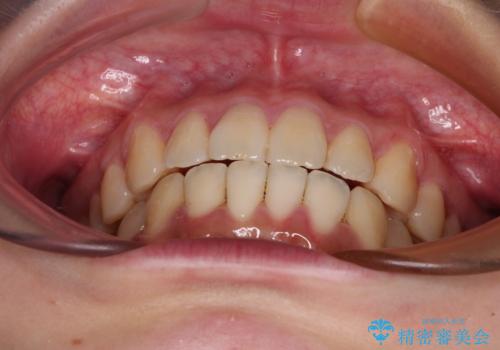

- 前歯の捻れを気にして来院された患者様です。

上顎前歯が捻れて前方に飛び出しており、下顎前歯もそれに沿うようにデコボコとなっていました。

IPR(歯と歯の間を削る処置)によりスペースを獲得して下顎前歯のデコボコを改善し、上顎前歯は下顎前歯と接する位置にまで引っ込めるように設定し、インビザラインにて矯正治療を行うこととしました。

しっかりと装着時間を守ってくださったので、予定通り1年強で治療を終えることができました。